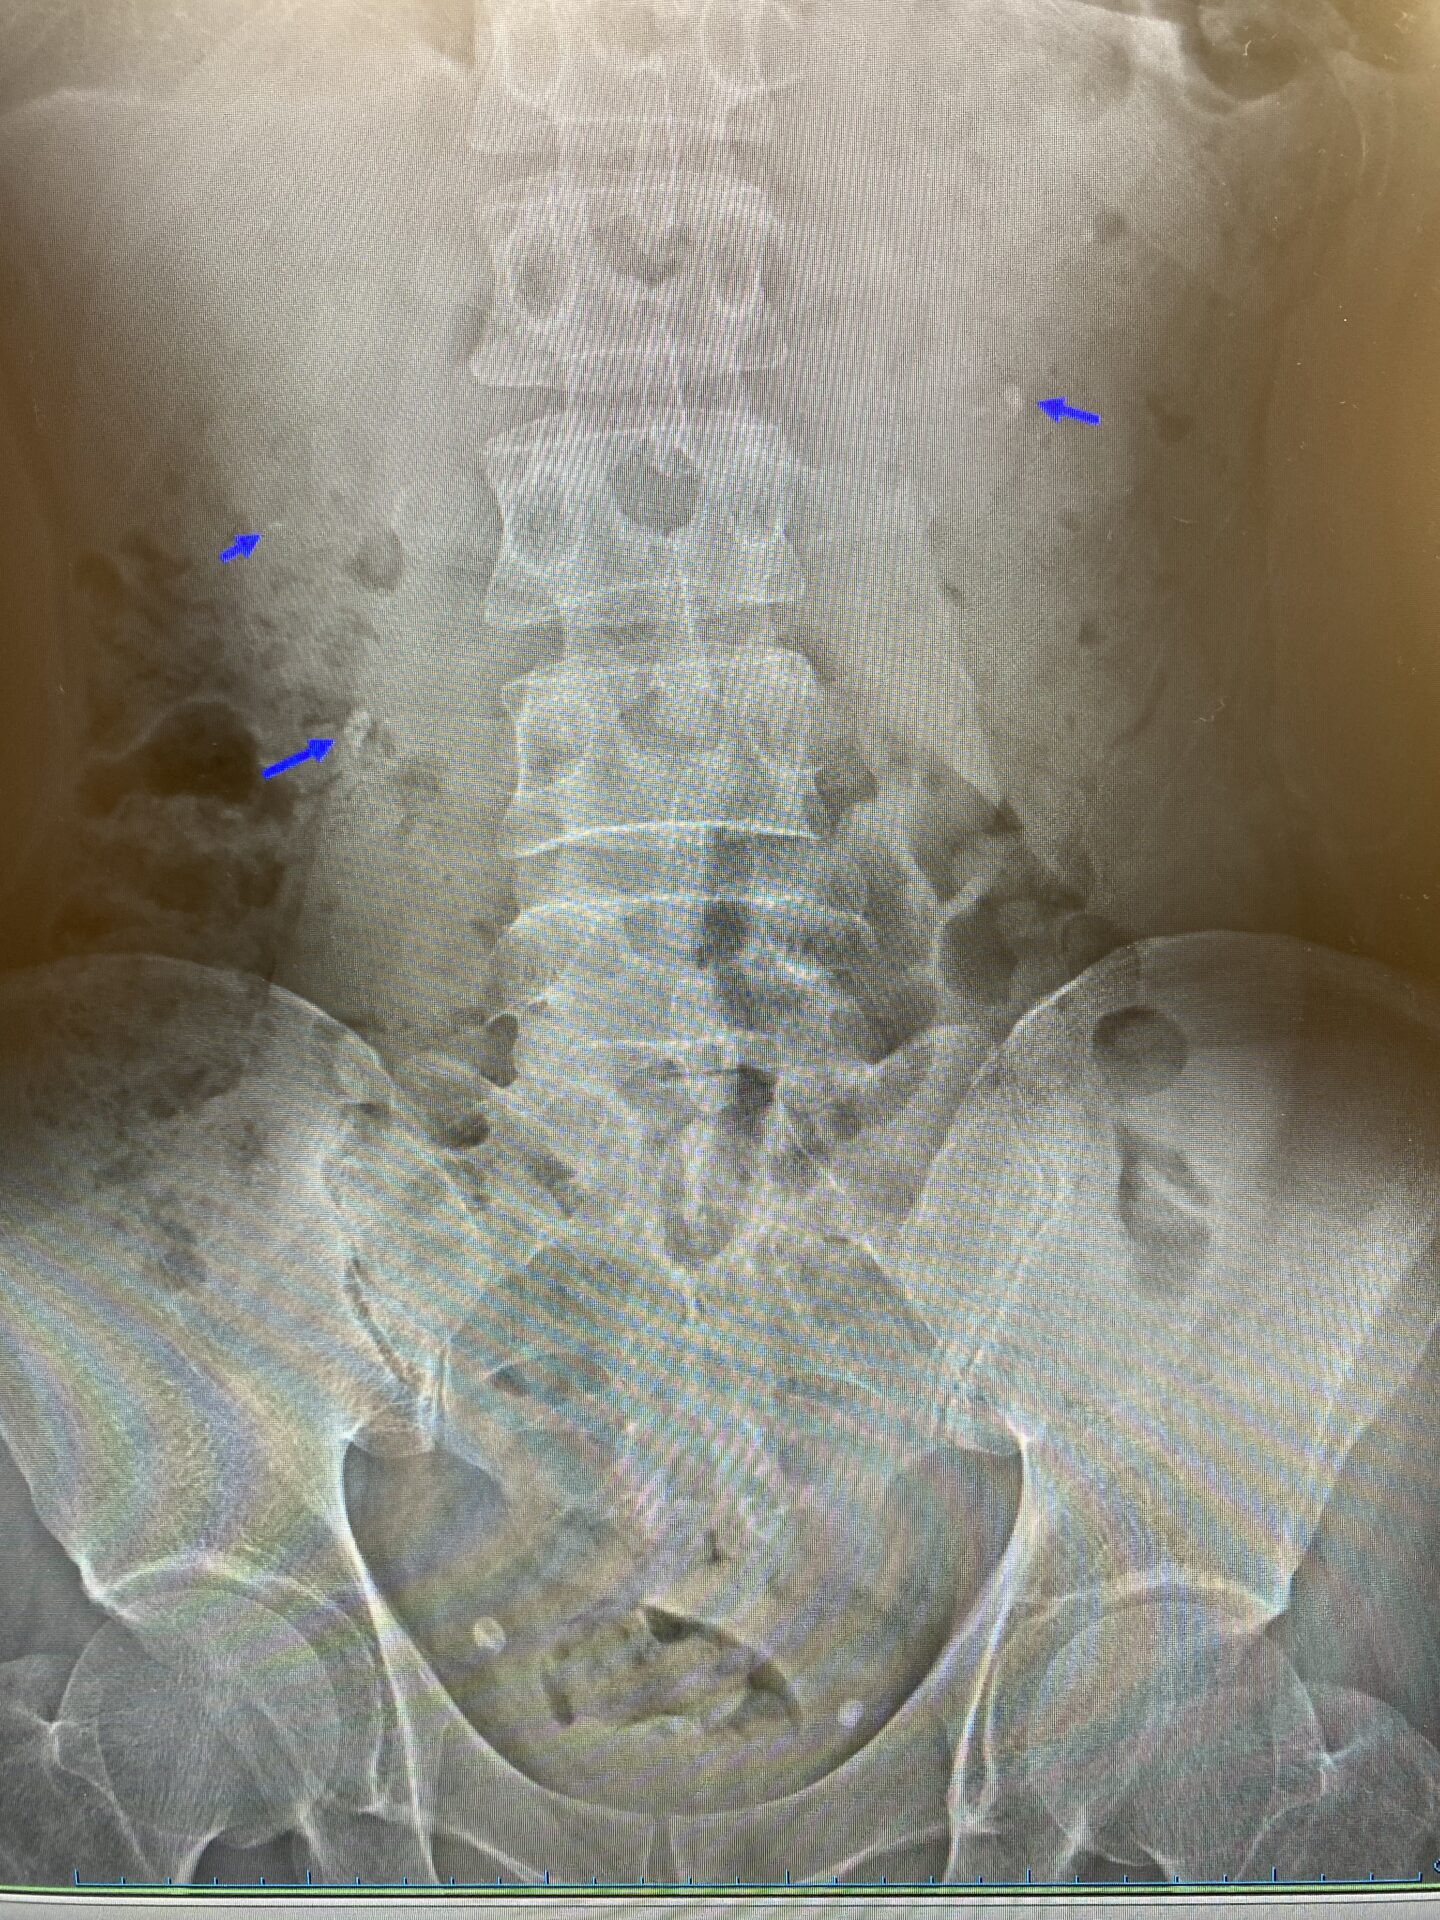

1例目は50歳台女性で、左背部痛を主訴に当院受診されました。エコー、x-p、CT上から左腎結石と左尿管結石が認められ、その後自然排石。その半年後にまた前回認められた左腎結石が左尿管内に下降してきたために再び左背部痛で当院受診され、その後自然排石。そして、さらにその3か月後に新たに出現した左尿管結石による左背部痛を主訴に当院受診され、その後自然排石。

2例目は40歳台男性で、肉眼的血尿と右背部痛を主訴に当院受診されました。エコー、x-p上から両側腎結石および右尿管結石が認められました。